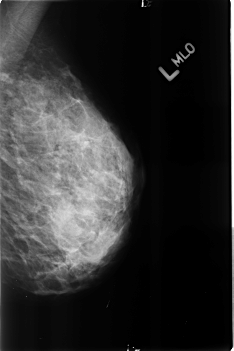

B_3191_1.LEFT_MLO

LEFT_MLO LINES 4552 PIXELS_PER_LINE 3032 BITS_PER_PIXEL 12 RESOLUTION 50 NON_OVERLAY